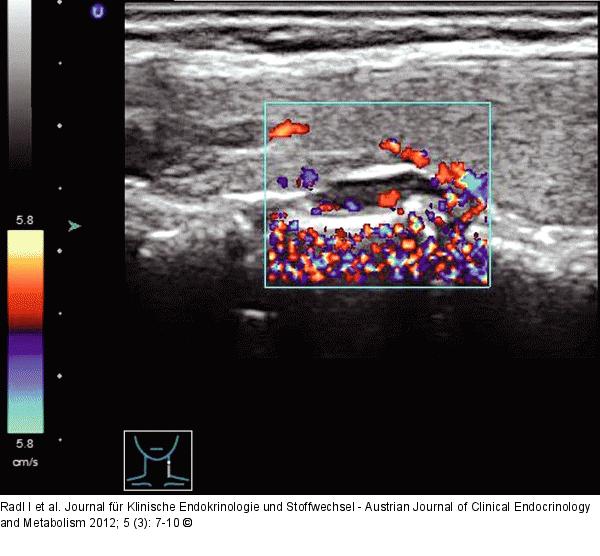

Abbildung 3: Nebenschilddrüsenadenom Primäres Nebenschilddrüsenadenom links einer 70-jährigen Patientin mit einer bogenförmig um das Adenom verlaufenden diffusen Hypervaskularisation. |

Abbildung 3: Nebenschilddrüsenadenom

Primäres Nebenschilddrüsenadenom links einer 70-jährigen Patientin mit einer bogenförmig um das Adenom verlaufenden diffusen Hypervaskularisation. |